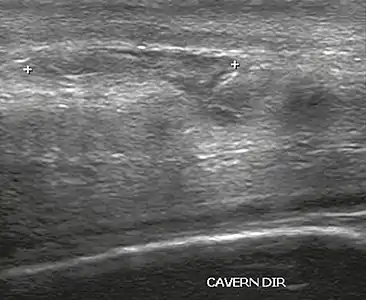

Venous drainage is performed by the deep and superficial dorsal veins of the penis. The dorsal arteries of the penis are located adjacent to the deep dorsal vein and a cavernous artery is located in the center of each corpus cavernosum. On color Doppler, the cavernous arteries present single phase flow. In the flaccid penis (Figure 3), the normal cavernous arteries show a systolic peak between 11 and 20 cm/s. At the beginning of erection, the systolic and diastolic flows undergo progressive increases. When vein occlusion begins, the diastolic flow decreases progressively, and once stiffness is established, it becomes negative.[1]